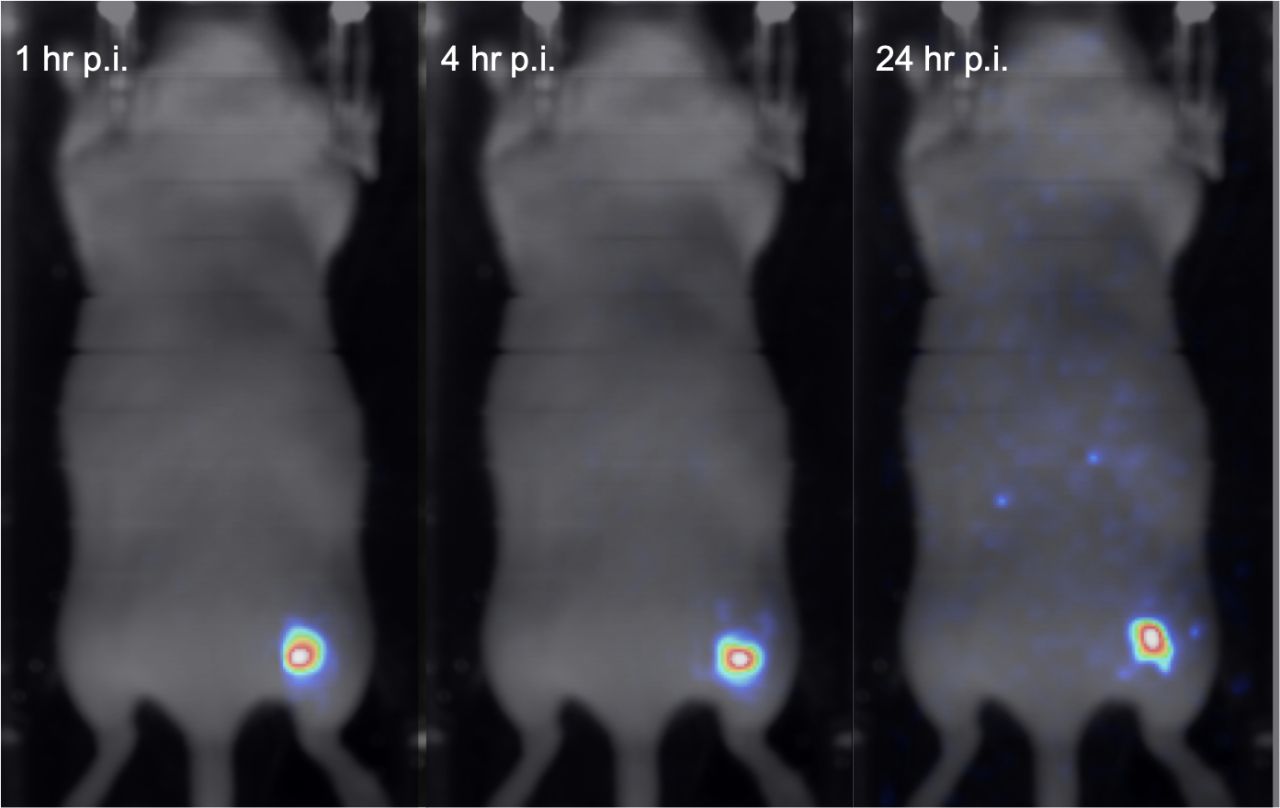

This week in BIOEMTECH Laboratories, we performed gold nanoparticle-labelled stem cells imaging in a mouse injury model, with our γ-eye system. NPs were labelled with In-111, then uptaken by stem cells and injected in the injury point. Images at several time points up to 24 hrs indicate a steady cell signal at the injury site with minimum uptake in other organs, predicting a successful stem cell therapy scheme!